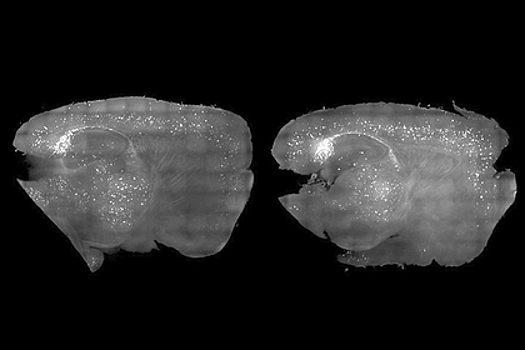

Ученые Массачусетского технологического института сумели с помощью света и звука очистить мозг мышей от вредных белков, провоцирующих у человека развитие болезни Альцгеймера — неизлечимой формы деменции, оканчивающейся смертью. Об этом сообщает издание Science Alert. Исследователи показали, что стробоскопы и слабый гул могут использоваться для генерации мозговых волн — гамма-ритма, который ухудшается при нейродегенеративном заболевании. В ходе эксперимента новый метод позволил снизить число скоплений патогенных белков и улучшить когнитивные функции у мышей, страдающих от состояния, аналогичного болезни Альцгеймера у людей. Визуальная стимуляция выражалась в мигании света 40 раз в секунду, а слуховая — в воздействии звука с той же частотой, то есть 40 герц. При этом наблюдались изменения в гиппокампе и префронтальной коре головного мозга грызунов и уменьшение бляшек, образованных тау-белками и амилоидами. Считается, что эти соединения играют одну из ключевых ролей в нейродегенеративных процессах. На данный момент от болезни Альцгеймера страдают 26 миллионов человек, и ожидается, что к 2050 году их число станет в четыре раза больше. Постепенно у пациентов происходит потеря долговременной памяти, возникают нарушения речи и когнитивных функций, в конце концов, больные теряют способность ухаживать за собой.